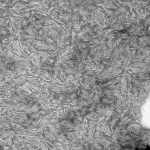

TEM of Human Recombinant Transthyretin L55P Mutant Filaments (SPR-464)